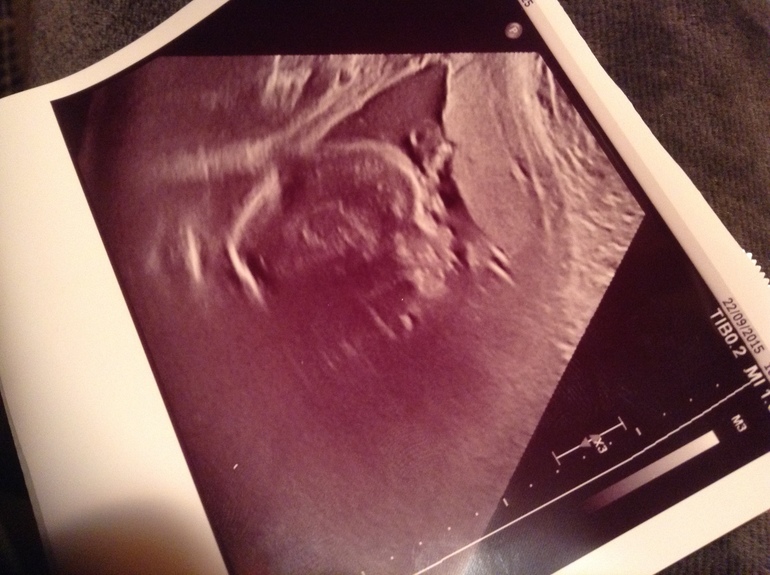

24 недели

От темени до крестца 22 см, вес 694 грамма.

И 100% девочка!!! Аринка

Воды внорме, шейка матки закрыта, 38мм

Фото личика в профиль, сказали расплывчатая из за лишнего моего веса, жир сьедает ультразвуковые лучи :(